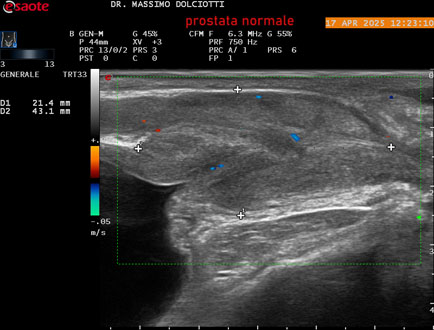

Data inserimento: 01/10/2025

Ecografia del: 17/04/2025

Strumento: Esaote MyLab Eight

Sonda: Convex Multifrequenza 1-8 MHz, Endocavitaria Multifrequenza 3-9 MHz e 3-13 MHz

Età Paziente: M 35 anni

Motivazione dell'esame: disuria.

Commento all'esame: le immagini ed il video documentano la prostata di ecostruttura regolare e morfovolumetria normale con diametro trasversale di 40 mm, diametro anteroposteriore di 21 mm e diametro longitudinale di 43 mm, con volume prostatico calcolato di 18 cc (v.n. < 20 cc), il profilo prostatico è regolare e netto, non si documentano calcificazioni intraghiandolari, la vascolarizzazione della ghiandola è normale. La vescicola seminale destra presenta diametro longitudinale di 44,4 x 7,8 mm, la vescicale seminale sinistra ha diametro longitudinale di 45,3 mm x 7,2 mm.

Conclusioni: prostata normale (normal prostate).

Presentazione: Dr. Massimo Dolciotti - Ancona

Elaborazione digitale: Andrea Dini - Ancona